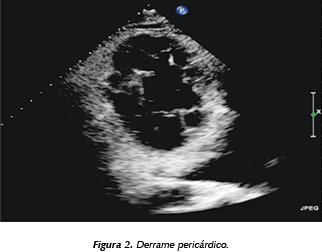

Introducción: La insuficiencia renal crónica siempre se ha asociado a diversos cambios ecocardiográficos; sin embargo, no tenemos una prevalencia de los cambios encontrados en nuestro centro. Objetivo: Describir los hallazgos ecocardiográficos encontrados en los pacientes con insuficiencia renal crónica en protocolo de trasplante, que acudieron a realizarse un ecocardiograma como parte de su valoración cardiovascular. Material y métodos: Estudio descriptivo, observacional, de corte prospectivo. Se incluyeron todos los pacientes que acudieron al estudio de ecocardiografía en el turno vespertino de agosto de 2009 a marzo de 2012. Resultados: De un total de 1906 pacientes, se encuentran 19.6% con insuficiencia renal (375 pacientes), tienen una fracción de expulsión del VI normal en el 80.6%, hipertrofia leve del VI 38.4%, hipertrofia moderada 11.2% y severa 0.5%, disfunción diastólica de cualquier grado 52.6% (grado 1: 20.3, grado 2: 20.3, grado 3: 12%) y alteraciones de la movilidad del ventrículo izquierdo se observa en el 15.2%. Derrame pericárdico de cualquier grado en el 22.3%, hipertensión arterial pulmonar en el 56.2% (leve 26.4, moderada 20.5, severa 9.3%), observa insuficiencia mitral en 58.3% (leve 38.6, moderada 14.4, severa 5.3%), insuficiencia aórtica 11.6%, insuficiencia tricuspídea moderada o severa en el 21%. Conclusión: Consideramos que por la alta prevalencia de alteraciones encontradas todos los pacientes con insuficiencia renal deben ir a un estudio de ecocardiograma, como parte del estudio integral para trasplante renal, incluso en aquellos asintomáticos cardiovasculares.